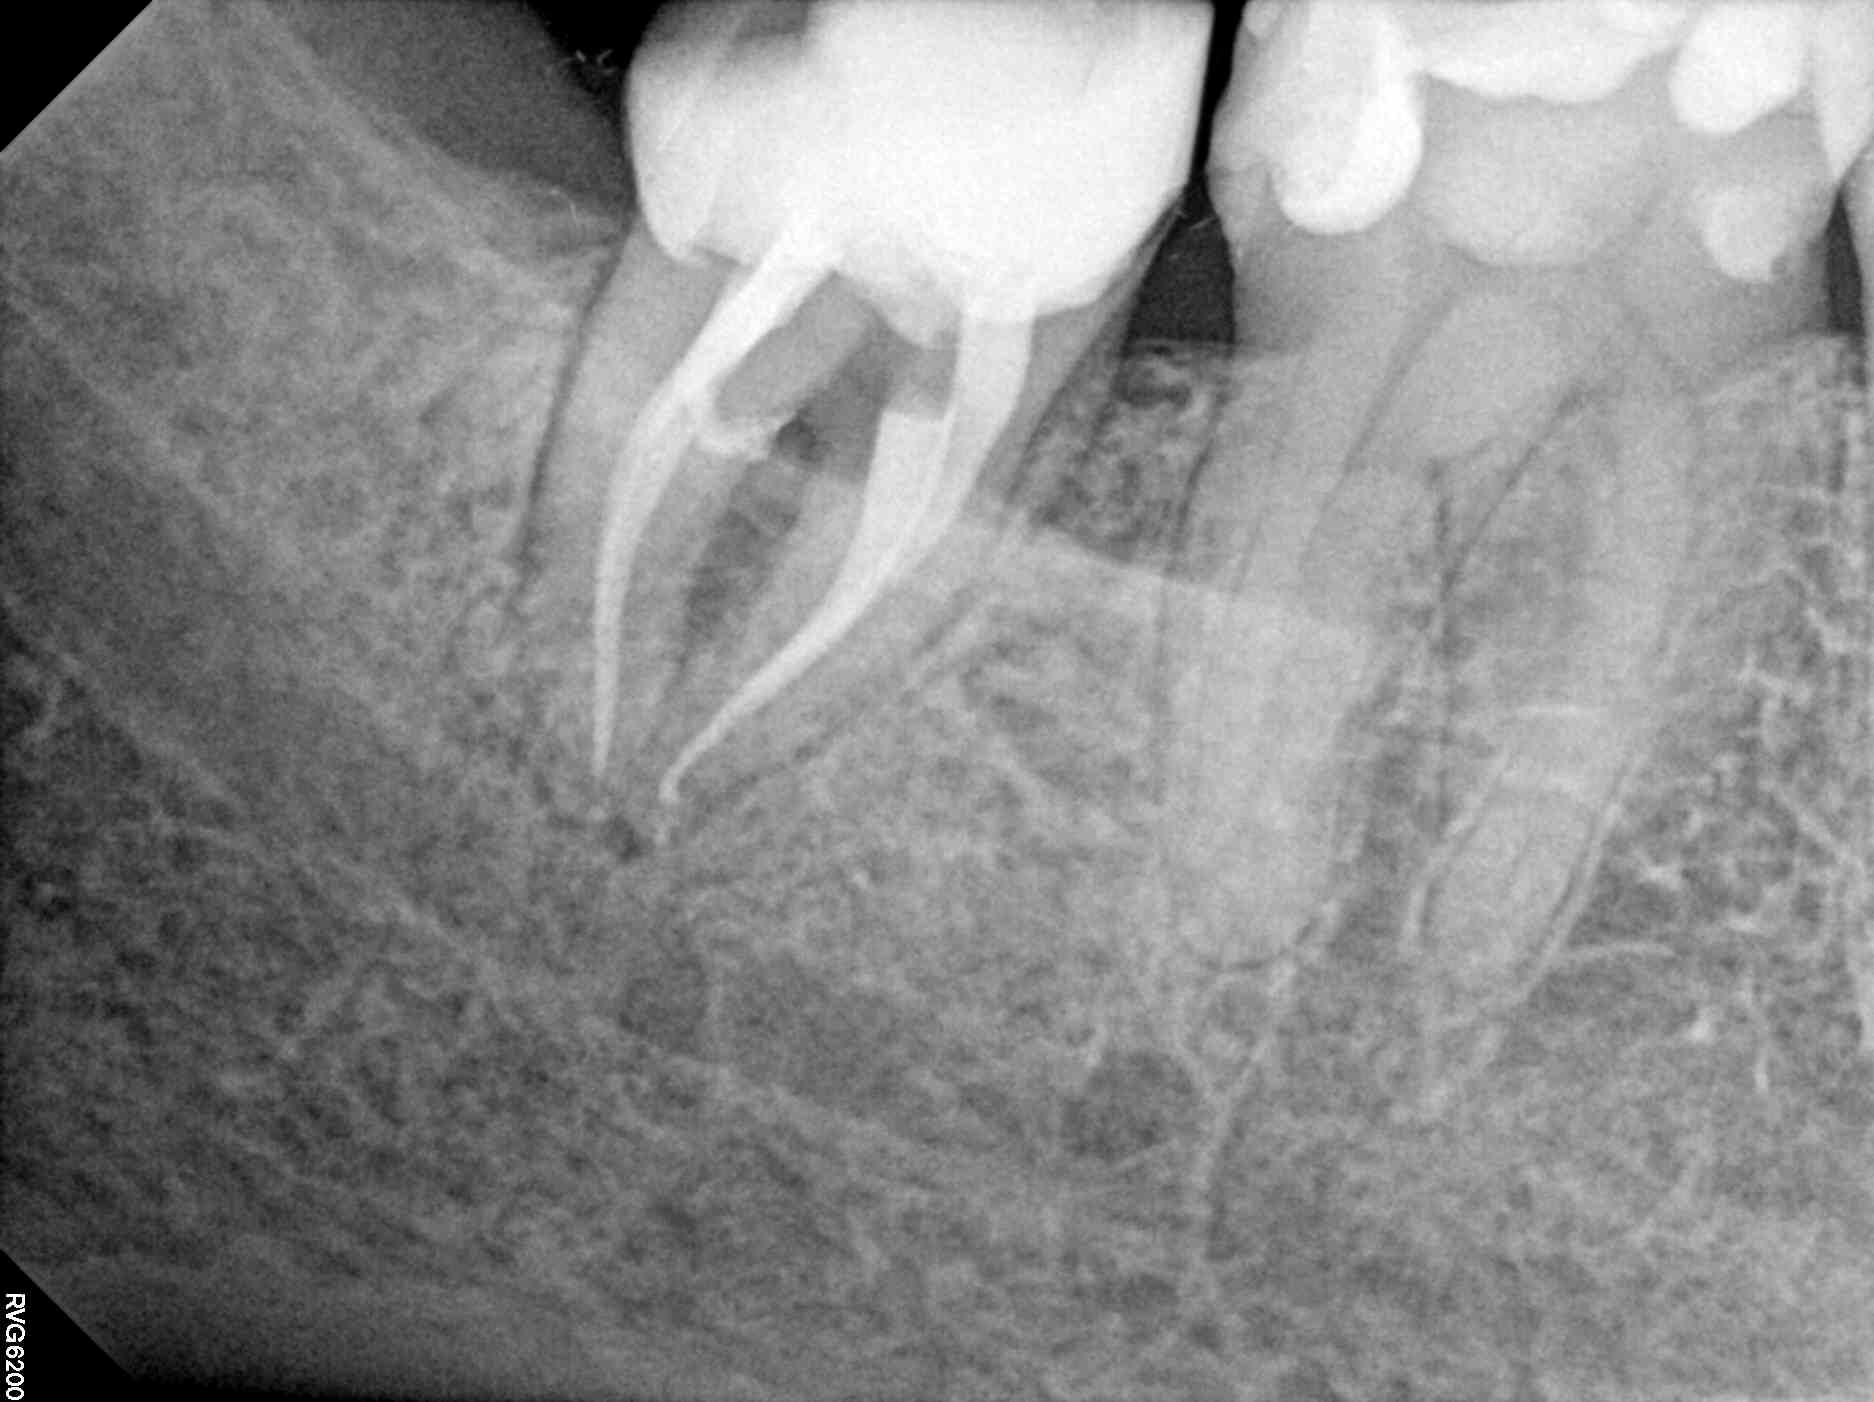

Beispiel 2: Vorher

Ausgedehnte Entzündung neben einem Implantat, bei diesem Überweisungsfall.

Beispiel 2: Nachher

Nur 6 Monate später ist die Entzündung fast vollständig zurückgegangen - Zahn und Implantat sind gerettet.